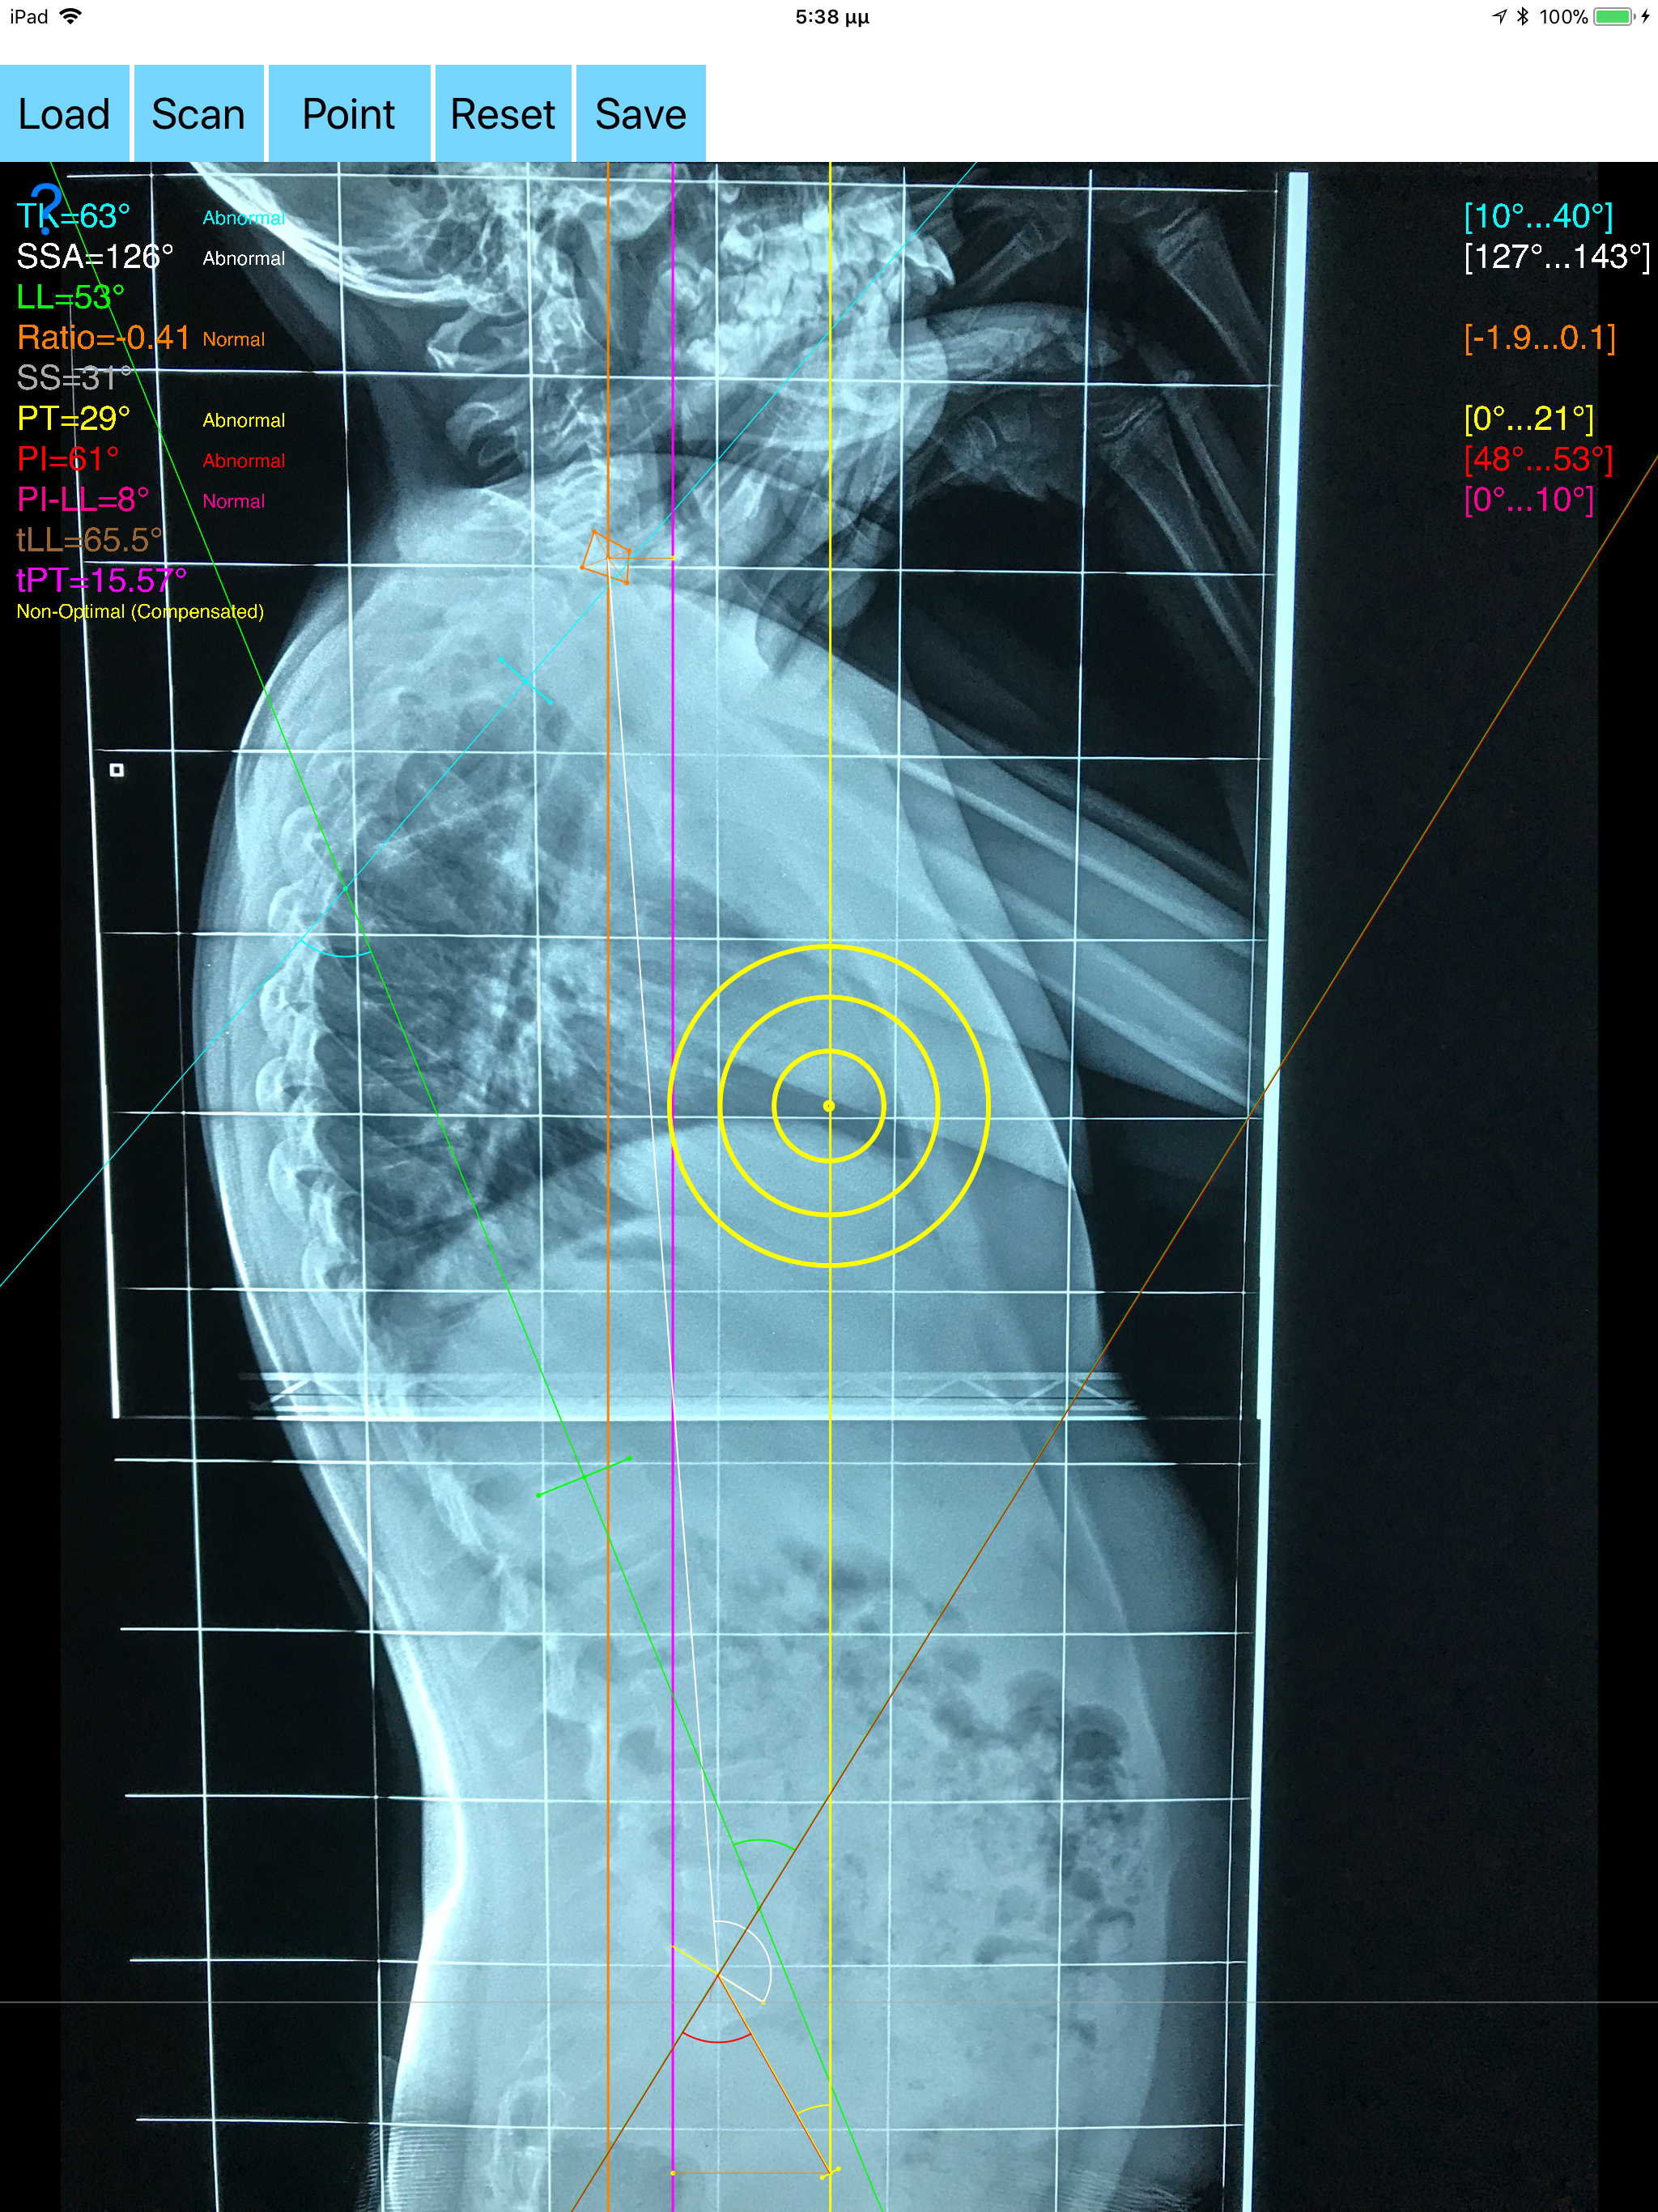

The assessment of global sagittal alignment and the compensatory mechanisms which are implicated in the spine and the spinopelvic jucture are of paramount importance for spine and joint replacement surgeon. The dynamic interplay between flexibility and balance around the axis of gravity determine the type and the amount of influence in spine and hips. Radiographic parameters to evaluate objectively the sagittal balance are Pelvic incidence (PI), Sacral slope (SS), Pelvic Tilt (PT), Lumbar lordosis (LL),Thoracic Kyphosis, C7 plumb line (C7PL) and its ratio. Drawings in patients X-rays and precise measurements are important in order to quantify the magnitude of spinal deformities, to monitor the success or failure of treatment and thus optimise the management of patients according to the severity of the imbalance. The Sagittal Balance App is medical software aimed for orthopaedic surgeons, providing tools that allow doctors to: -Securely import medical images directly from the camera or stored photos. -By marking several points at the image of X-ray, the App calculates and offers a very convenient way to determine the most accurate possibly way at once, Pelvic incidence (PI), Sacral slope (SS), Pelvic Tilt (PT), Lumbar lordosis (LL), thoracic kyphosis, C7 plumb line (C7PL), C7PLD/sfd ratio, PI–LL, theoretical normal pelvic tilt (tPT),theoretical normal L1-S1 lumbar lordosis (tL1S1), Spino-sacral angle (SSA) According to measured parameters the app categorizes the severity of the imbalance of spine, in three different stages: optimal balanced, balanced with compensatory mechanisms and imbalanced. -Save the planned images, for later review or consultation.The measured values are compared by normal reference databases and also data are exported as txt file, ready to print or to input as cells to excel for research. -The app also allows the calculations of centroids after choosing points in vertebra body in independent manner from order. All information received from the software output must be clinically reviewed regarding its plausibility before patient treatment! Sagittal Balance App indicated for assisting healthcare professionals. Clinical judgment and experience are required to properly use the software. The software is not for primary image interpretation. In a busy everyday practice, the examiner have to draw lines in X-rays or in clinical settings, this it is time consuming and cumbersome. Accessory instruments like protractors, hinged goniometers, well sharped pencils, rulers or even transparent papers must be available. The app offers a very convenient and accurate way to perform most common radiographic measurements for spine, and spinopelvic juncture in a blink of an eye in front of your screen. The build in feature of the app, allows results to be categorized may help decide what could be considered normal or pathologic. The app is not a simple goniometer, is an enhanced product which helps to monitor objectively the course of the treatment and evaluate optimally the spine. This App is particular useful especially in clinical settings where you need a quick results without losing time. Please see tutorial videos at the developer’s web site www.orthopractis.com Reference databases 1.Legaye J, Duval-Beaupe`re G, Hecquet J, Marty C (1998) Pelvic incidence: a fundamental pelvic parameter for three-dimensional regulation of spinal sagittal curves. Eur Spine J 7(2):99–103 2. Cavanilles-Walker JM, Ballestero C, Iborra M, Ubierna MT, Tomasi SO (2014). "Adult Spinal Deformity: Sagittal Imbalance". International Journal of Orthopaedics.